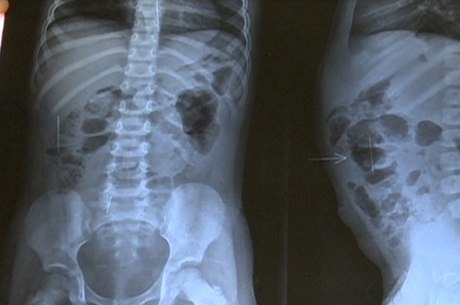

Uma menina de apenas três anos tem ao menos três agulhas de costura pelo corpo e quatro já foram removidas. A tia da criança denunciou à polícia que o padrasto é suspeito da agressão.

A garota vivia com a mãe na cidade de Atalaia, mas mudou-se para a casa de uma tia em Jacaré dos Homens, cidade do interior de Alagoas. A menina se queixou de dor e, após exames, descobriram as agulhas.

A mulher fez a denúncia e o suspeito, Ronaldo de Oliveira, foi detido em Atalaia para depoimento. Ele negou que tivesse colocado as agulhas e afirmou que a própria enteada fez as perfurações. Ele foi liberado.

A mãe da vítima também foi ouvida pela polícia e disse já ter retirado quatro agulhas do corpo da filha e não soube dizer quem as teria colocado. A polícia informou que segue investigando o caso.